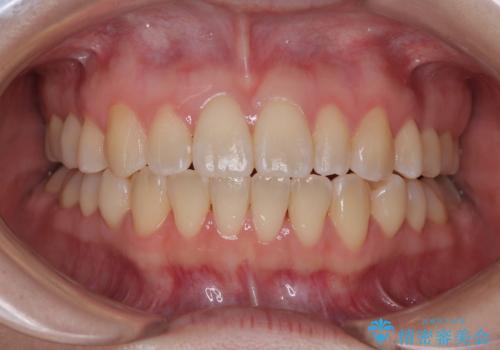

早く・確実に歯並び改善|目立ちにくいワイヤー矯正

- 治療期間

- 1年6ヶ月

- 治療回数

- 10-30回

- 94万円(税込)費用は治療当時の料金となります